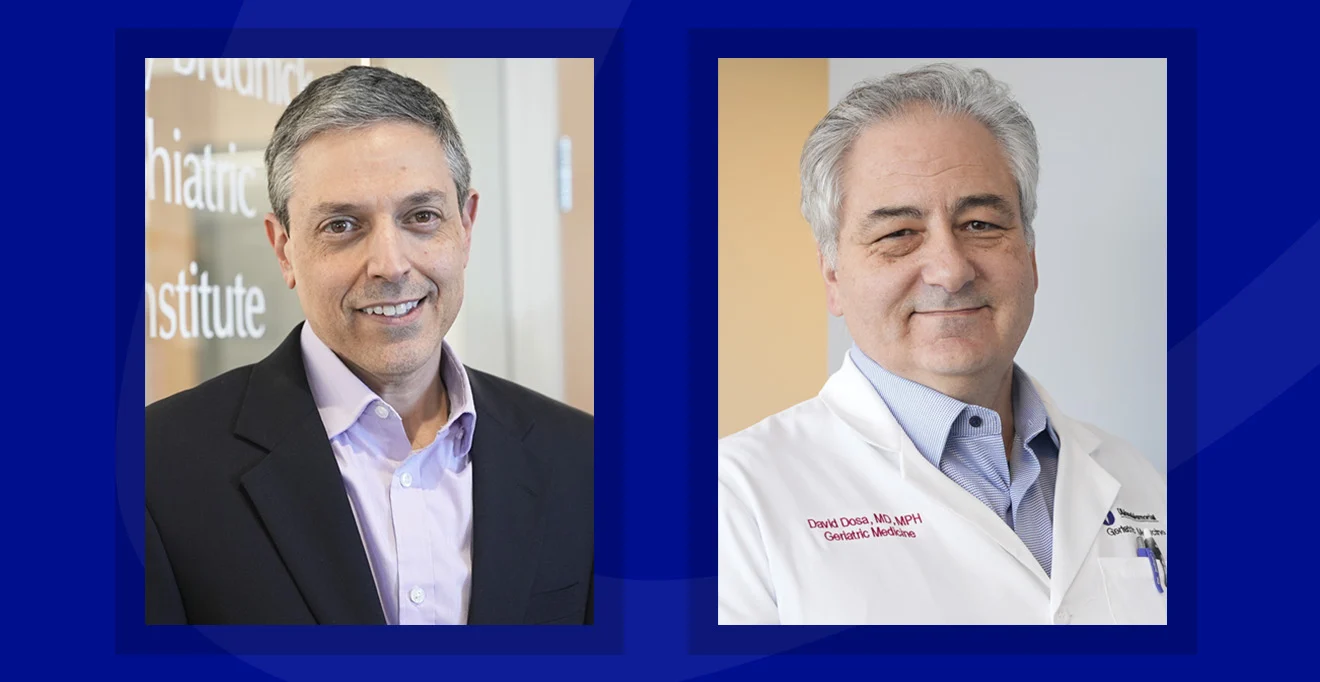

David Dosa and Andrew Tapper named to newly established endowed chairs